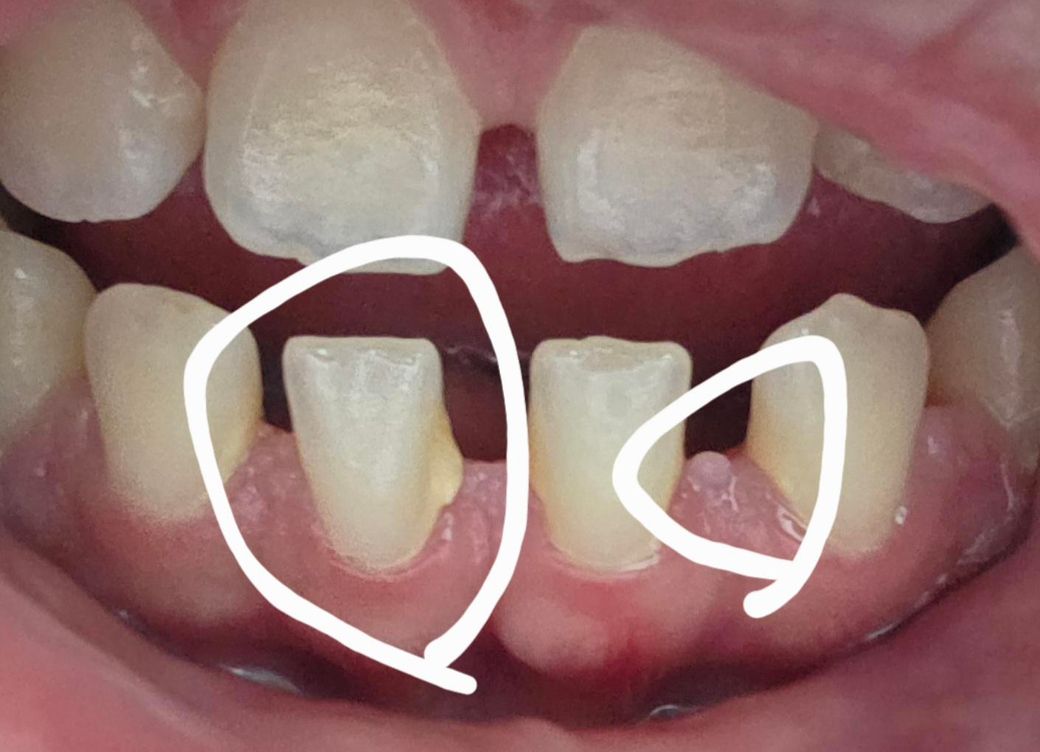

이거 혹시 치석인가요? 궁금합니다..

두번째 하얀색원에 이거 오돌토돌하게 나있는 이게 뭔지 모르겠습니다

2. 잇몸 염증으로 보입니다 전반적으로 잇몸관리해주세요

사진상으로 왼쪽에 보이는것은 치석이 맞으며 오른쪽에 보이는것은 치석이라기 보다 치아 조직으로 보입니다.

정확한 확인을 위해서 치과에서 진료를 받아 보는것을 권유드립니다.